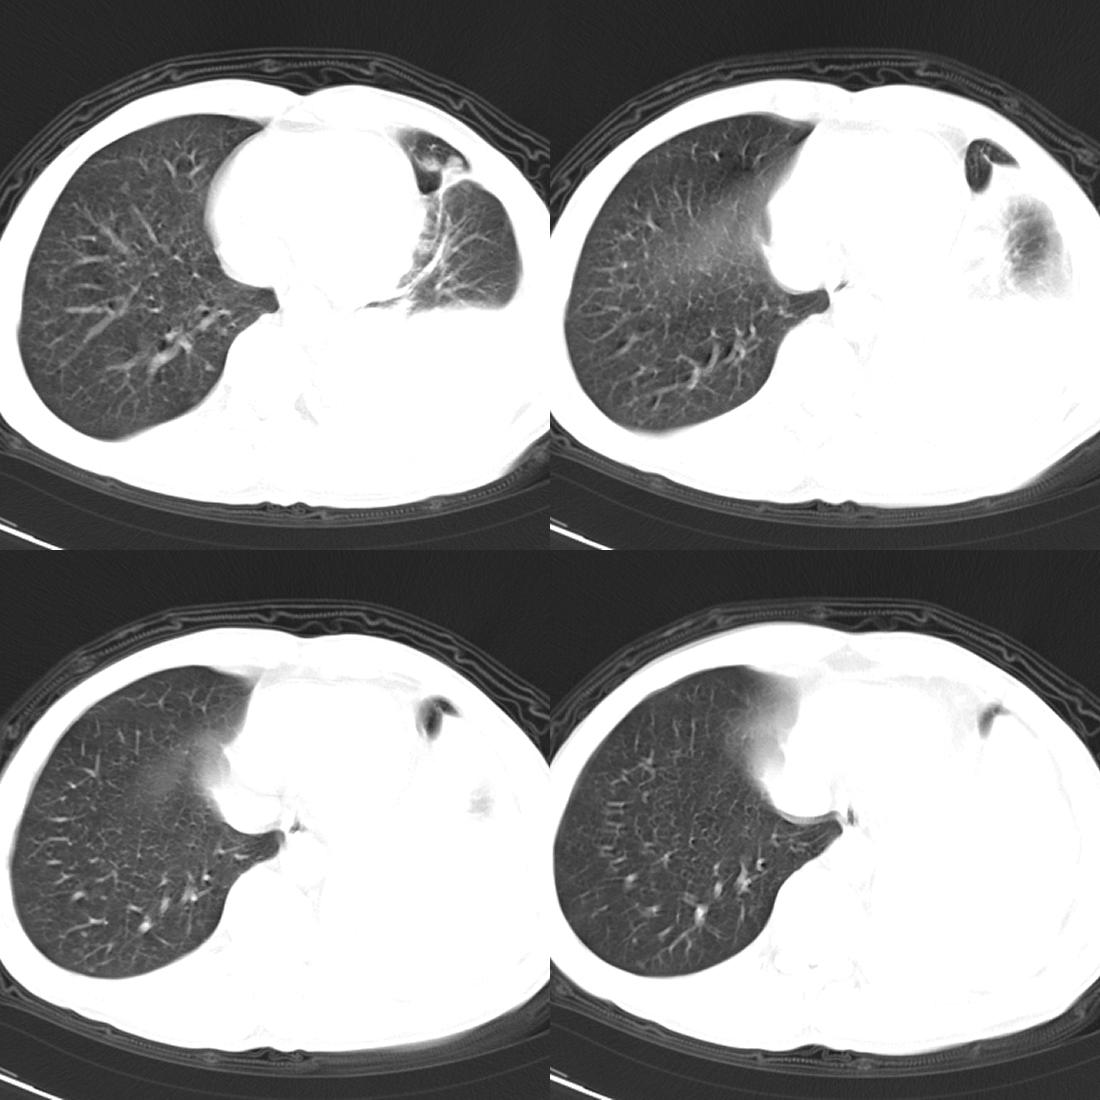

m42y,反复胸背痛数月。无明显的咳嗽、咯痰、咯血症状。

左肺不张 并大量胸腔积液.建议气管镜 除外占位..

左肺上叶周围型肺癌伴肺\\胸膜\\肋骨\\胸椎横突转移,左侧胸腔积液.

左侧椎体、横突、肋骨呈溶骨性破坏,半左侧胸腔中等量积液;左肺尖部可见一肿块影,边界欠清;多考虑恶性骨肿瘤,不除外肺尖部转移性表现可能。

左肺除有肺不张,胸腔积液,尚有斑点、斑片、结节及兔耳征,纤维化等病灶,除考虑除外占位,还应考虑结核所致。。。现在结核病又有泛发趋势。。

左肺上叶周围型肺癌伴双肺\\胸膜\\肋骨\\胸椎横突转移,左侧胸腔积液.

关注中 左上肺应该有个包快吧,还有左肺是部分不张